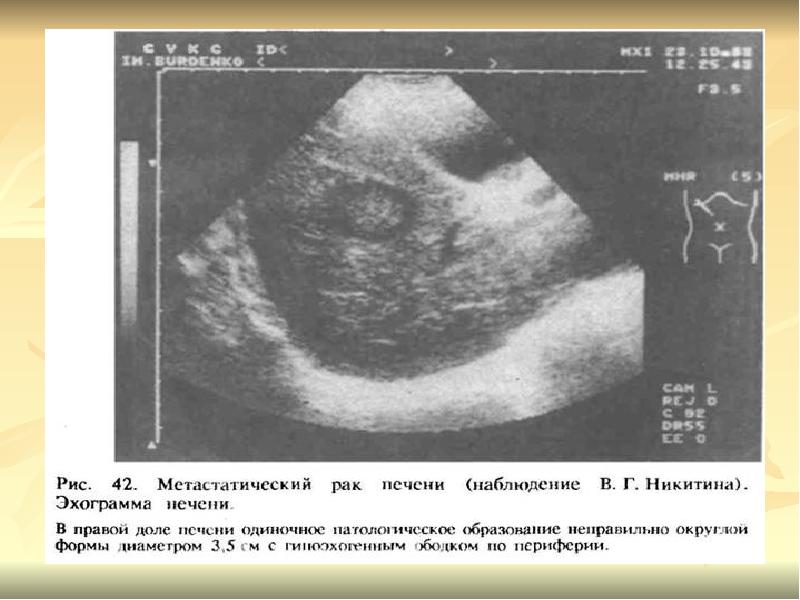

Метастатические поражения печени в ультразвуковом изображении характеризуются